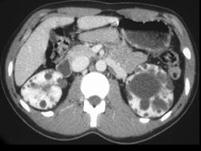

问题 女,34岁,血肌酐、尿素氮增高,请根据所示图像,选择最可能诊断 ( )

选项 A、双侧多发性肾囊肿 B、多发囊肿性肾发育不全 C、多囊肾 D、囊性肾癌 E、双肾脓肿

答案 C